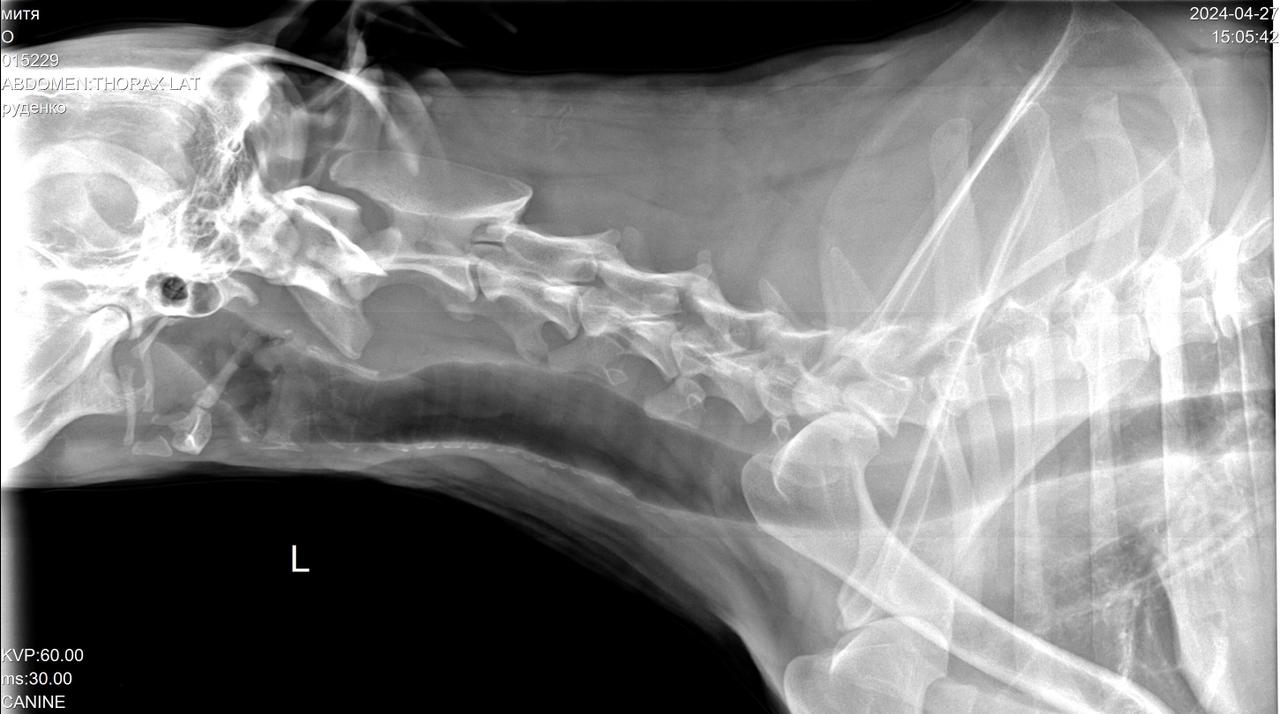

Сегодня Катюша возила Митю на рентген.

IMG-20240427-WA0028.jpg

IMG-20240427-WA0029.jpg

IMG-20240427-WA0030.jpg

IMG-20240427-WA0031.jpg

IMG-20240427-WA0032.jpg